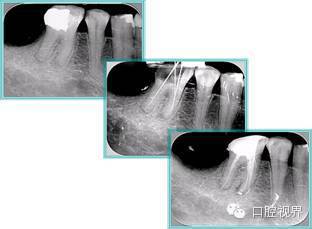

共有 4 张 X 线片,分别是术前、诊断丝 、主牙胶尖确认、术后。

( 1 )术前:术前 X 线片用来了解牙齿的大概情况。术前预期为多根牙时 X 线片应偏头拍摄。

( 2 )诊断丝:根据术前 X 线片进行开髓、根管的初步预备后,需要插入诊断丝,用来指示工作器械位置。常用 10 号或 15 号扩大器作为诊断丝插入牙髓腔。

( 3 )主牙胶尖确认:通过术前预期和诊断丝诊断,明确工作长度、牙根走向,进行根管预备。之后应进行主牙胶尖(中锉)确认,已明确根管是否适合充填。

( 4 )术后:观察治疗效果。